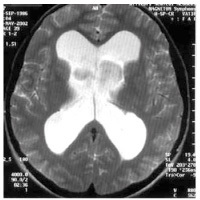

Un patient présente une marche à petit pas, avec anomalie des réflexes posturaux et une ataxie. Une IRM séquence T2: est réalisée: quel diagnostic?

multiples lacunes des noyaux gris centraux car multiples hypersignaux T2

(état lacunaire)